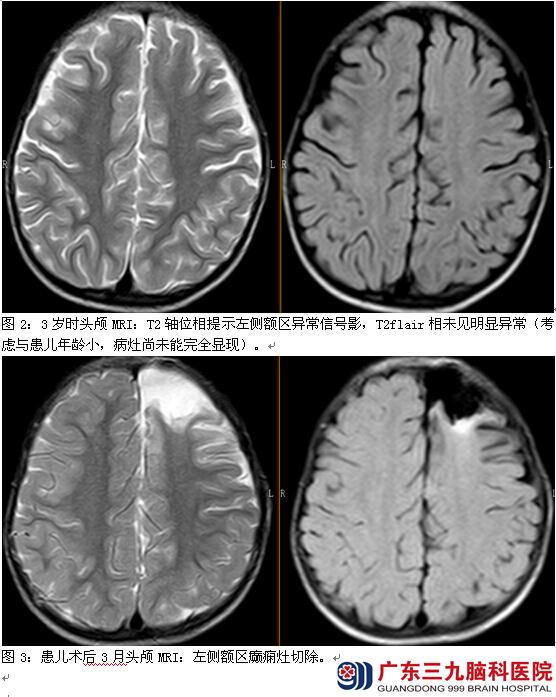

起病后先后服用癫痫宁、硝基安定、得理多、氯硝西泮、奥卡西平、妥泰、左乙拉西坦、拉莫三嗪、加巴喷丁、唑尼沙胺、安定、咪达唑仑静,每日仍有30~70次发作。既往史及个人史均无特殊,智力运动发育正常。多次复查头颅MRI+增强均未见明显异常。神经系统无明显异常。VEEG检查报告:异常脑电图。左额颞区多量慢波活动;发作期:临床:右侧肢体强直,尖叫(7次),右侧肢体强直阵挛,尖叫(1次)。EEG:左额起源。考虑为药物难治性癫痫,局灶起源。纳入术前评估,脑磁图提示间期癫痫放电位于左额、左额颞。3岁4月龄行左侧额极病变切除,随访2年6月无发作。

【讨论】患儿为学龄前儿童,电-临床-症状学提示为局灶性癫痫,结合患儿头颅MRI多次提示未见异常,考虑多方面因素,其一,患儿年龄小,髓鞘发育尚未完成,脑组织含水量更多,导致病灶很难被发现,因此需要癫痫专业医生结合患者症状学才能发现病灶。因此,随着年龄增长,幼年患儿有必要反复多次复查头颅MRI明确病灶。本例患者致痫灶考虑为左侧额区,为优势半球可能,一次性外科手术得以获益。获益依赖于术前评估患儿致痫灶与功能区相距较远。